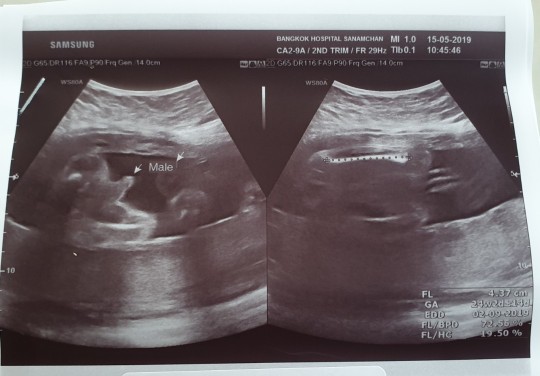

ชายจ้าแม่

ผช.จ้า ^^